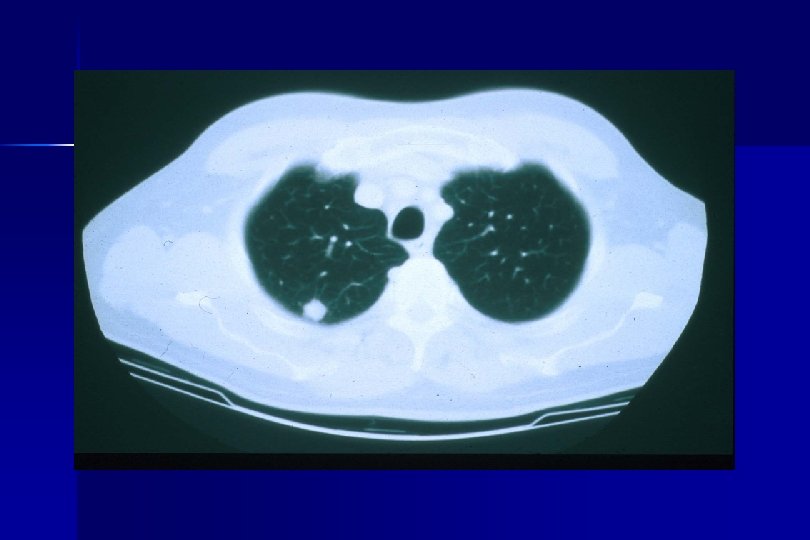

Eligibility Criteria Part I: Pre-Operative Criteria (Pre-Registration/Randomization): ● Patients must have a suspicious lung nodule for clinical Stage I NSCLC. ● Patient must have a mass ≤ 3 cm maximum diameter by CT size estimate: Clinical stage Ia or selected Ib (i. e. , with visceral pleural involvement. ● Patient must have a CT scan of the chest with upper abdomen within 60 days prior to date of pre-registration.